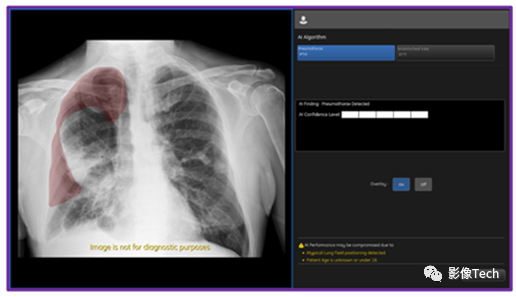

Critical Care Suite 2.1是一套用于自动分析正面胸部X射线影像(从数字X射线系统上采集)的AI算法,可以部署在多个计算平台上,包括PACS、本地、云端以及X射线成像系统。Critical Care Suite 2.1是Critical Care Suite算法系列的最新版本,能够检测和定位气胸(气体进入胸膜腔造成的积气状态)的位置。原来的算法已经能给疑似气胸的危重病例进行优先级排序,如图:

现在一旦AI算法检测到有胸发生,系统就会立刻发出通知,在相关医疗设备或PACS中显示相关信息,帮助医护人员迅速了解患者的情况。

面对这个问题,GE医疗在不断变革移动X射线设备,这次更新的Critical Care Suite 2.1算法(嵌入在移动X射线设备上AI算法的集合)便是证明。这次更新后的算法精准度很高,大型气胸定位的准确率达到了100%,而小型气胸定位的准确率也有96%。同时,算法还能以94%的概率避免出现误报。目前,来自临床的数据表明该技术用处很大。使用该技术后,需要手术进行干预的气胸的报告生成时间减少了57%,临床医生检测出小型气胸的概率增加了17.7%。